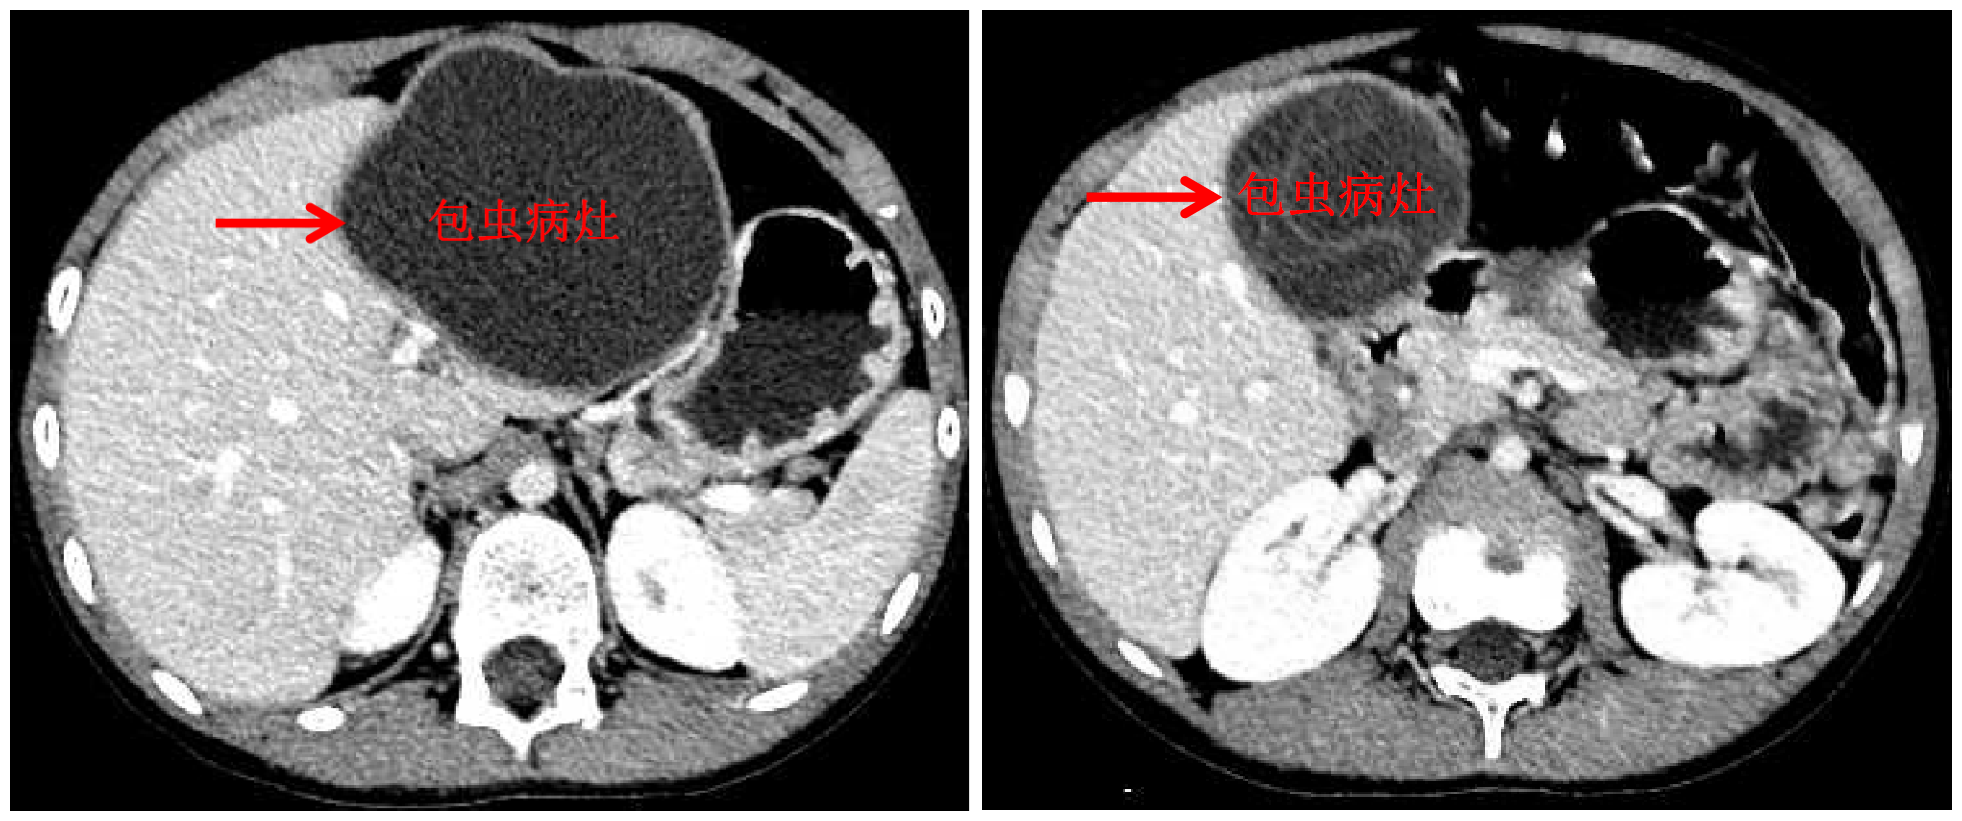

国庆前,8岁的小扎西被父亲带到了西藏大学附属拉萨市人民医院普外科,此次距离孩子确诊肝包虫病已有一年之久。腹部影像显示,小扎西体内的囊型肝包虫病已经侵袭了左肝大部。

包虫病灶

术前三维定量化手术规划及虚拟手术

经三维定量化手术评估及虚拟手术,王学栋认为,肝脏两处病灶虽然巨大,但都位于左半肝,可以挑战腹腔镜解剖性左半肝切除术。9月23日,王学栋联手拉萨市人民医院普外科平措主任等一同为小扎西实施了手术,同术前预测,由于包虫巨大导致术中肝门解剖极为困难,王学栋果断改为前入路左半肝切除术,并同时保留了肝中静脉。在该院强丹主任带领的麻醉科团队和手术室团队的保障下,手术顺利完成,出血量仅100ml。